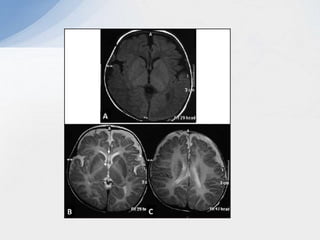

De-myelination Vs hypo-myelination

Demyelination:

• Prominent T2 hyperintensity.

• Prominent T1 hypointensity.

Hypomyelination:

• Mild T2 hyperintensity.

• Variable T1 signal (hypo, iso or hyperintense).